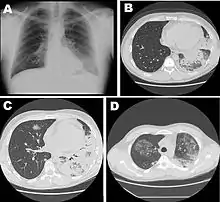

La radiographie du thorax peut montrer un infiltrat pulmonaire ainsi qu'un épanchement pleural. Les images peuvent persister un certain temps après la fin du traitement[26].